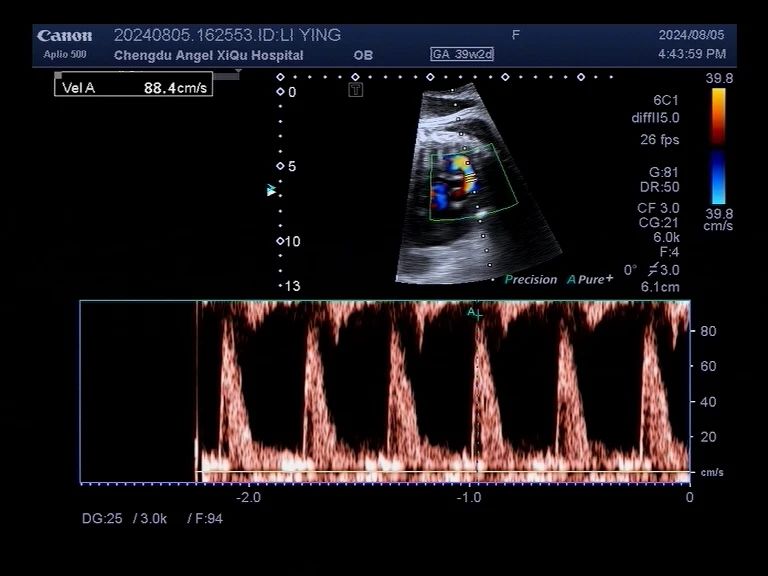

▪l女士胎儿心脏b超

b超提示:胎儿心脏动脉导管提前收缩及早闭伴右心增大、三尖中-重度返流。

经肖兵院长、超声科等多科室联合会诊,考虑胎儿动脉导管提前收缩或早闭,情况很危急,建议立即终止妊娠。这个宝宝的动脉导管接近闭合,这就如同一扇不知道什么时候就会关闭的门,一旦关闭,宫内胎儿的生命就岌岌可危。跟时间赛跑,抢在“关门”前让宝宝安全出生是保证安全的唯一方法。